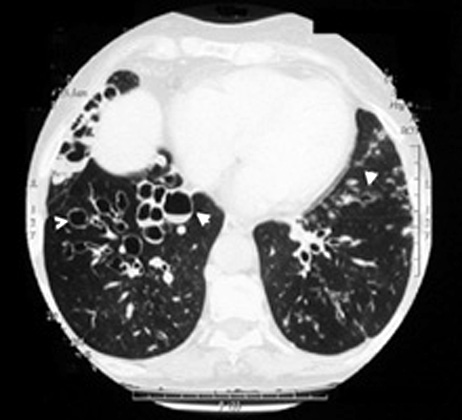

Bronchiectasis

Dilated bronchi with peribronchial fibrosis, visualized in various cuts of CT as cystic spaces, tubular shadows and branching densities.